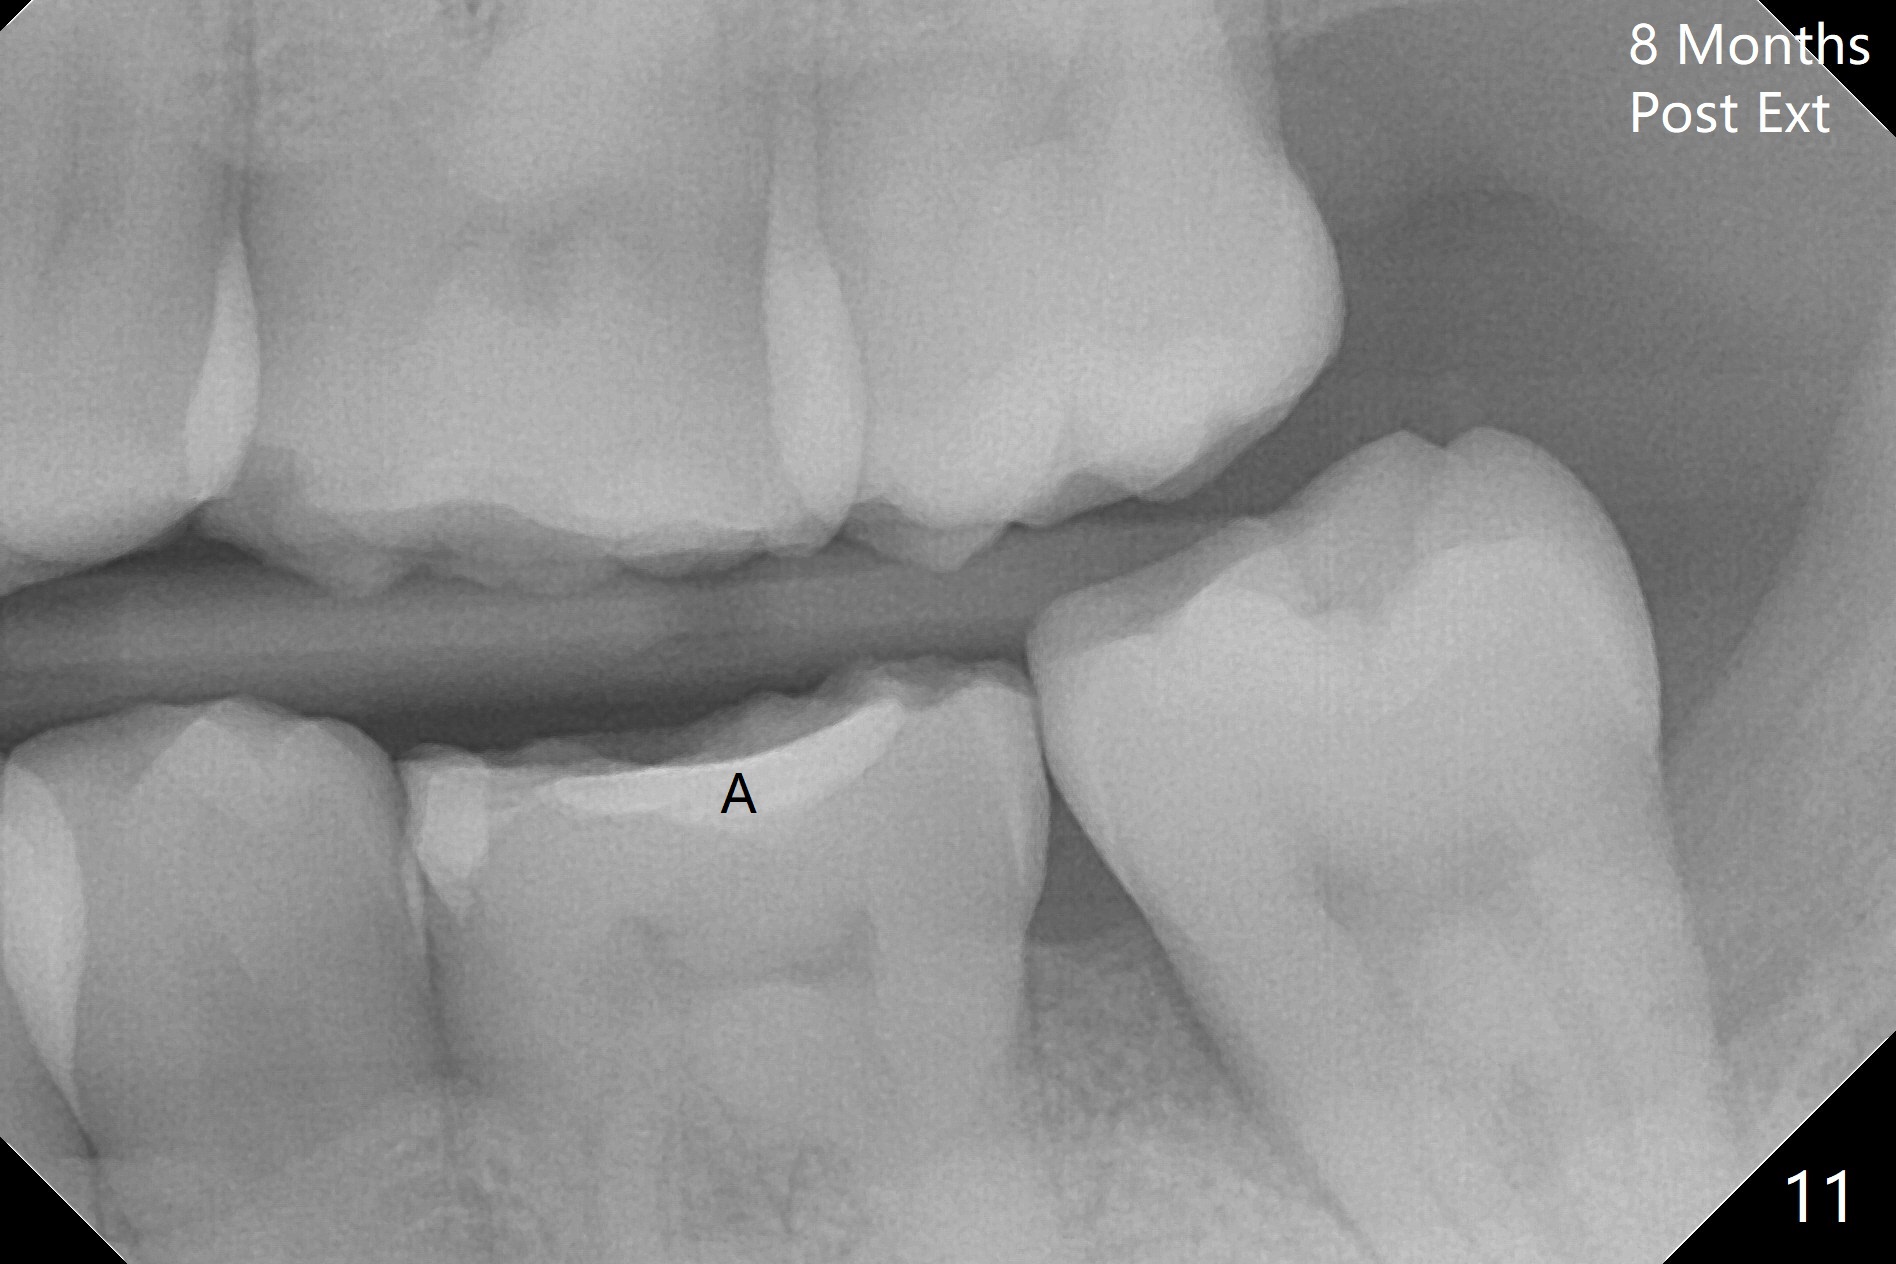

Photos are taken to show occlusal wear (bruxism) of the teeth #31 and 17 (Fig.7,8) prior to #17 extraction. Osteogen plug is placed in #17 socket after extraction and SRP at #18. The bone height at #18 distal seems to increase 2 years 4 months post extraction (Fig.9-12). The 1st molars have enamel hypoplasia with occlusal wear. In addition, occlusion is abnormal. There is no centric occlusion, partially contributing to periodontitis at #15 and 18. Crown is planned at #19 because of loss of occlusal amalgam (Fig.11 A, 12). Orthodontics may be required, although 2 insurances do not have orthodontic coverage for adults.